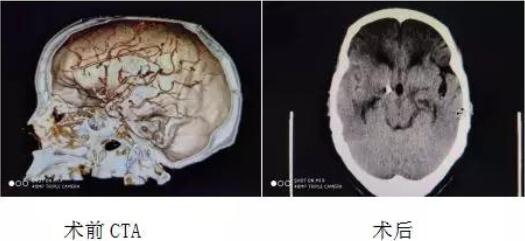

成人导航 成功开展颅内动脉瘤夹闭术及脑血管造影动脉瘤栓塞术